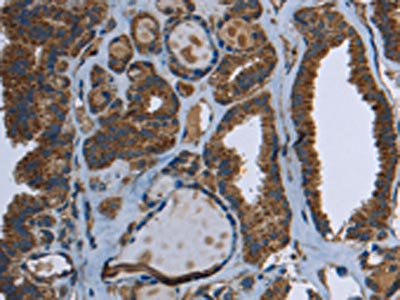

The image on the left is immunohistochemistry of paraffin-embedded Human thyroid cancer tissue using CSB-PA138466(GCK Antibody) at dilution 1/40, on the right is treated with fusion protein. (Original magnification: ×200)

The image on the left is immunohistochemistry of paraffin-embedded Human liver cancer tissue using CSB-PA138466(GCK Antibody) at dilution 1/40, on the right is treated with fusion protein. (Original magnification: ×200)